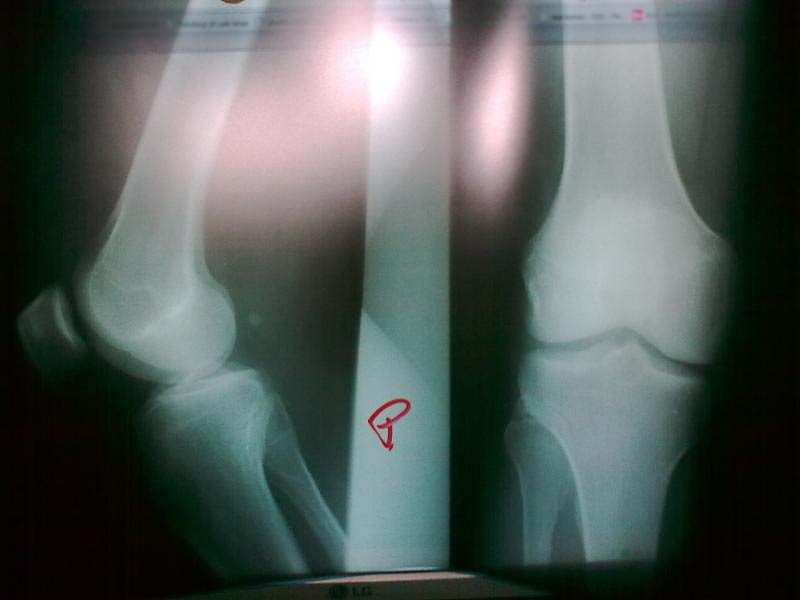

Moje prawe kolano :)

Niech na zdjęciu będzie uśmiechnięta osoba trzymająca kartkę papieru, na której jest napisane "e-kwidzyn jest fajny". Obok osoby ma być monitor, na którym będzie widać moje prawe kolano :)